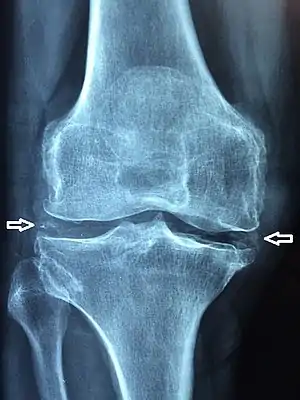

| X-ray of a knee with chondrocalcinosis | |

Chondrocalcinosis or cartilage calcification is calcification (accumulation of calcium salts) in hyaline cartilage and/or fibrocartilage.[1] It can be seen on radiography.

Chondrocalcinosis can be visualized on projectional radiography, CT scan, MRI, ultrasound, and nuclear medicine.[1] CT scans and MRIs show calcific masses (usually within the ligamentum flavum or joint capsule), however radiography is more successful.[1] At ultrasound, chondrocalcinosis may be depicted as echogenic foci with no acoustic shadow within the hyaline cartilage.[7] As with most conditions, chondrocalcinosis can present with similarity to other diseases such as ankylosing spondylitis and gout.[1]